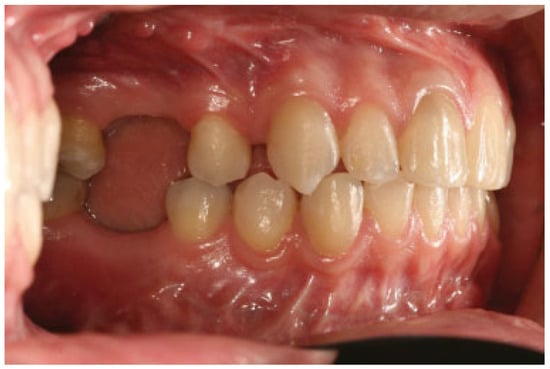

:Case Report